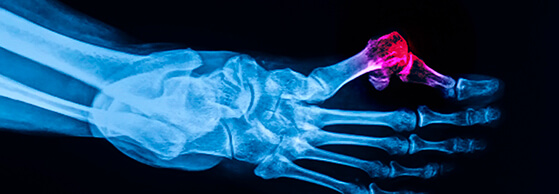

Bunion

He will also order an x-ray of your foot to determine the severity of the bunion condition.